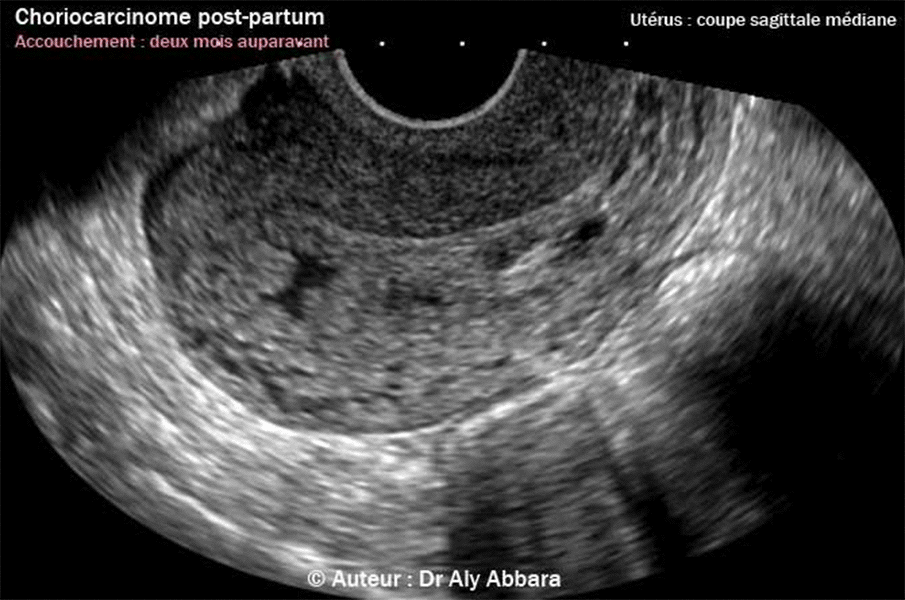

Images montrant l'un des aspects échographiques du choriocarcinome de l'utérus après une grossesse de déroulement normal et un accouchement normal, deux mois auparavant. |

| Il s'agit d'une masse hétéro-échogène mesurant 44 x 19 mm en coupe sagittale médiane, et 19 x 18 mm en coupe transverse. Elle occupe la cavité du corps utérin tout en infiltrant sa paroi postérieure ; cette zone d'infiltration paraît hypervascularisée quand on active le mode Doppler couleur (Dynamic-Flow). Les annexes utérines sont normales. Ce choriocarcinome a été mis en évidence deux mois après un accouchement normal suite à une grossesse ayant un déroulement habituel, sans incident particulier. En effet la période du post-partum fut marquée par de multiples épisodes de métrorragie d'abondance très variable. Le dosage de β-hCG plasmatique à la date de la réalisation de ces images était d'environ 118 000 UI/litre. Le diagnostic anatompathologique de choriocarcinome fut réalisé sur des débris endométriaux prélevés lors d'un curetage biopsique et hémostatique très prudent de l'endomètre. Le choriocarcinome est une tumeur hautement maligne et le plus souvent métastatique. 50 % des cas de choriocarcinome sont mis en évidence suite à une môle hydatiforme, 25 % des cas suite à un avortement spontané et enfin, 25 % des cas suite à une grossesse normale et un accouchement normaux. L'incidence du choriocarcinome est de l'ordre de 1/40 000 grossesses. d’après Dodson, 1983, en cas de môle complète, le risque d'évoluer vers un choriocarcinome est de l'ordre de 1/30 (1/6000 pour un avortement spontané et 1/40 000 pour une grossesse normale). |